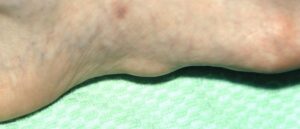

Лечение подошвенного фиброматоза

У людей иногда появляются различные болезни на ногах. Одной из таких считается подошвенный фиброматоз, который представляет собой образование упругих узлов на поверхности стопы. Данное заболевание приносит дискомфорт и неудобства. Если фиброму на подошве не лечить, она мешает ходьбе, вызывая болезненные ощущения. К тому же важно правильно дифференцировать этот недуг, так как есть риск вовремя не …